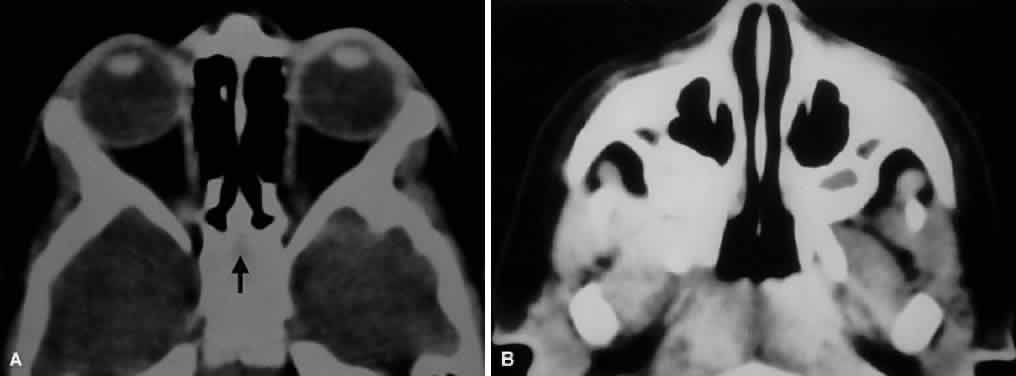

The ethmoidal sinuses can be observed to begin to take shape between the 6th and 8th weeks of gestation and are fully developed at birth. The remaining paranasal sinuses develop much later, with the sphenoid and frontal sinuses continuing to pneumatize into adolescence or early adulthood (Fig. 5). This accounts for the high incidence of orbital cellulitis from adjacent ethmoiditis in children. The lamina papyracea separating the orbit from the ethmoidal air cells is thin and perforate in children, providing easy access for microbial spread. Because the remainder of the sinuses are rudimentary in children, they are rarely the source of orbital infectious processes. Most of the orbital bones are formed during the 3rd month, although their ossification ensues over the next several months. At term, the orbit is nearly hemispheric, and the bony perimeters closely hug the globe.17

Fig. 5. Axial CT of paranasal sinus development in a 2-year-old child. A. Note that the ethmoid air cells are pneumatized, but the future sphenoid sinus is seen only as a faint lucency (arrow) within surrounding bone. B. Rudimentary maxillary sinuses have already partially pneumatized.